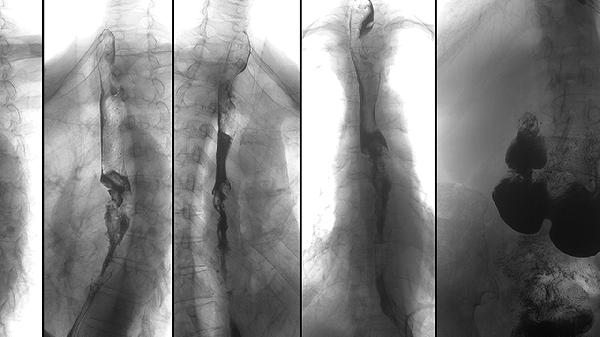

脊柱活動(dòng)受限是強(qiáng)直性脊柱炎進(jìn)展期的典型表現(xiàn),由于韌帶骨贅形成和關(guān)節(jié)強(qiáng)直導(dǎo)致?;颊呖赡艹霈F(xiàn)頸椎、胸椎和腰椎各個(gè)方向的活動(dòng)度下降,如前屈、后伸、側(cè)彎和旋轉(zhuǎn)受限。嚴(yán)重時(shí)脊柱可能完全強(qiáng)直,呈現(xiàn)典型的竹節(jié)樣改變?;顒?dòng)受限通常從腰椎開(kāi)始,逐漸向上發(fā)展,最終可能影響整個(gè)脊柱。